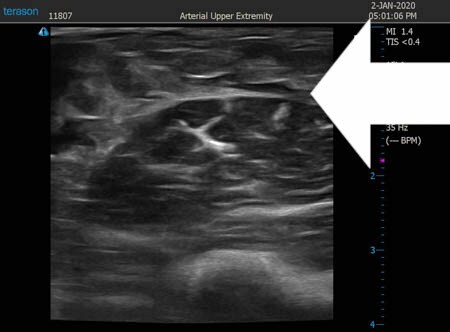

いつものように3Dタッチビュー(超音波)で

皮下脂肪層を評価してみましょう。

右二の腕

↓ ↓ ↓